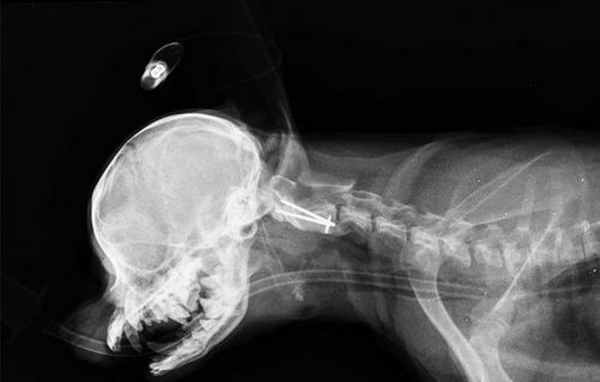

Рентген диагностика атлантоаксиальной нестабильности, в плане принятия решения о проведении хирургической ее коррекции, не информативна и в нашей клинике не проводится. Наиболее полное представление о степени выраженности данной патологии, так же как и о наличии сопутствующих изменений в нервной системе, можно получить только на основании данных нейровизуальных исследований, таких как МРТ или КТ- томографии.

Применение нативного кт позволяет получить надежные доказательства (является методом выбора) наличия атланто-аксиальной нестабильности и оверлеппинга однако следует помнить, что последний может быть динамическим и меняться при определенных положениях головы.

Той терьер с атланто-аксиальной нестабильностью

Краниография собаки с вентральной стабилизацией С1-С2.